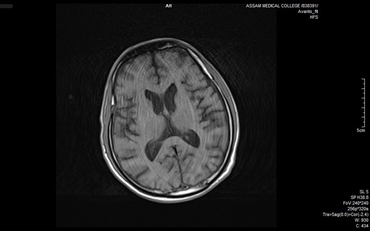

Skull bone marrow plays a critical role in central nervous system (CNS) immunity by housing specialized immune cells that interact directly with cerebrospinal fluid (CSF), influencing neuroinflammation and neurodegeneration. Unlike peripheral marrow, skull marrow uniquely contributes to brain immune responses. Non-invasive imaging techniques such as TSPO-PET show strong potential for detecting skull marrow activity in conditions like Alzheimer’s and multiple sclerosis, offering an alternative to invasive bone marrow biopsies (Table 3). Additionally, intracalvarial drug delivery, which bypasses the blood-brain barrier, significantly enhances therapeutic delivery to the brain. This emerging approach holds promise for improving treatment outcomes in CNS disorders and warrants further investigation.